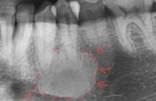

3 |

Quiste radicular |

Imagen radiolúcida, redonda u ovalada y unilocular, que se presenta en la región periapical y puede estar rodeada por hueso cortical delimitada por una línea radiopaca continua lo cual indica la existencia de hueso esclerótico.3,7 |

|